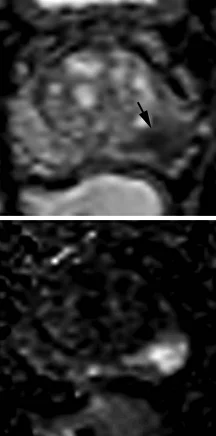

Peripheral Zone (PZ)

Нормальная диффузия

Слабая гиперинтенсивность

Очаг гипоинтенсивен на ADC, изо- или гиперинтенсивен на DWI. Либо сильно гипоинтенсивен на ADC, либо сильно гиперинтенсивен на DWI, но не одновременно и там и там.

Очаг выраженного ограничения диффузии (гипо- на ADC, гипер- на DWI), менее 1.5 см

То же что и PIRADS 4, только размером более 1.5см

Нет раннего накопления контрастного препарата, или диффузное мультифокальное накопление, не соответствующее очагу на Т2 и DWI

Раннее накопление контрастного препарата (раньше или одновременно с нормальной тканью железы), соответствует очагу на Т2 и DWI